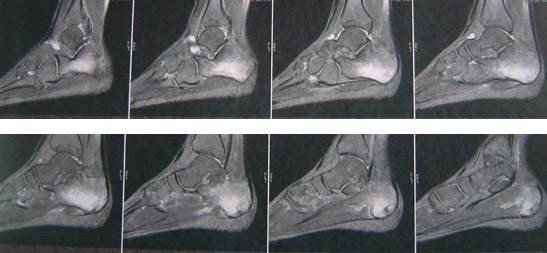

L’IRM des 2 calcanéums a montré un œdème important de la trame osseuse lié à la contusion avec suspicion de fissures.

Nous ne montrons qu’un seul pied en IRM, l’autre a présenté la même évolution.

Un des 2 pieds :